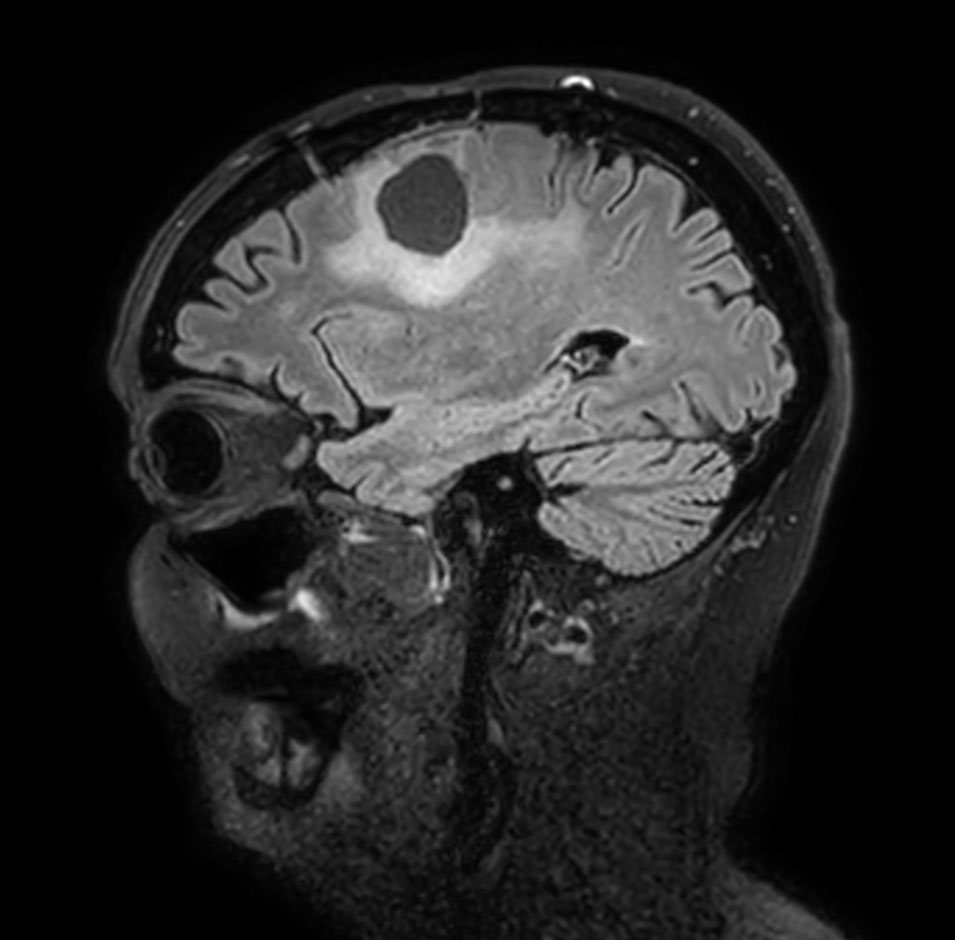

Sagittal 3D FLAIR